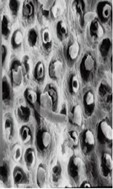

采用牙科用磷酸酸蝕劑對牙本質(zhì)表面進(jìn)行酸蝕處理,能有效去除玷污層,使管周牙本質(zhì)脫礦溶解,牙本質(zhì)小管開口處管徑增大,膠原纖維網(wǎng)暴露,見圖2。這種結(jié)構(gòu)能夠使粘接劑與管間牙本質(zhì)形成微機械粘接,且有利于粘接劑滲入牙本質(zhì)小管內(nèi)形成樹脂突,從而增大粘接強度。

圖2 牙本質(zhì)表面酸蝕前后形態(tài)掃描電鏡圖示例

如圖2所示,(左)酸蝕前,牙本質(zhì)有玷污層覆蓋;(右)酸蝕后,表面較粗糙,玷污層已被去除,部分牙本質(zhì)小管開放,管間牙本質(zhì)膠原纖維網(wǎng)充分暴露。